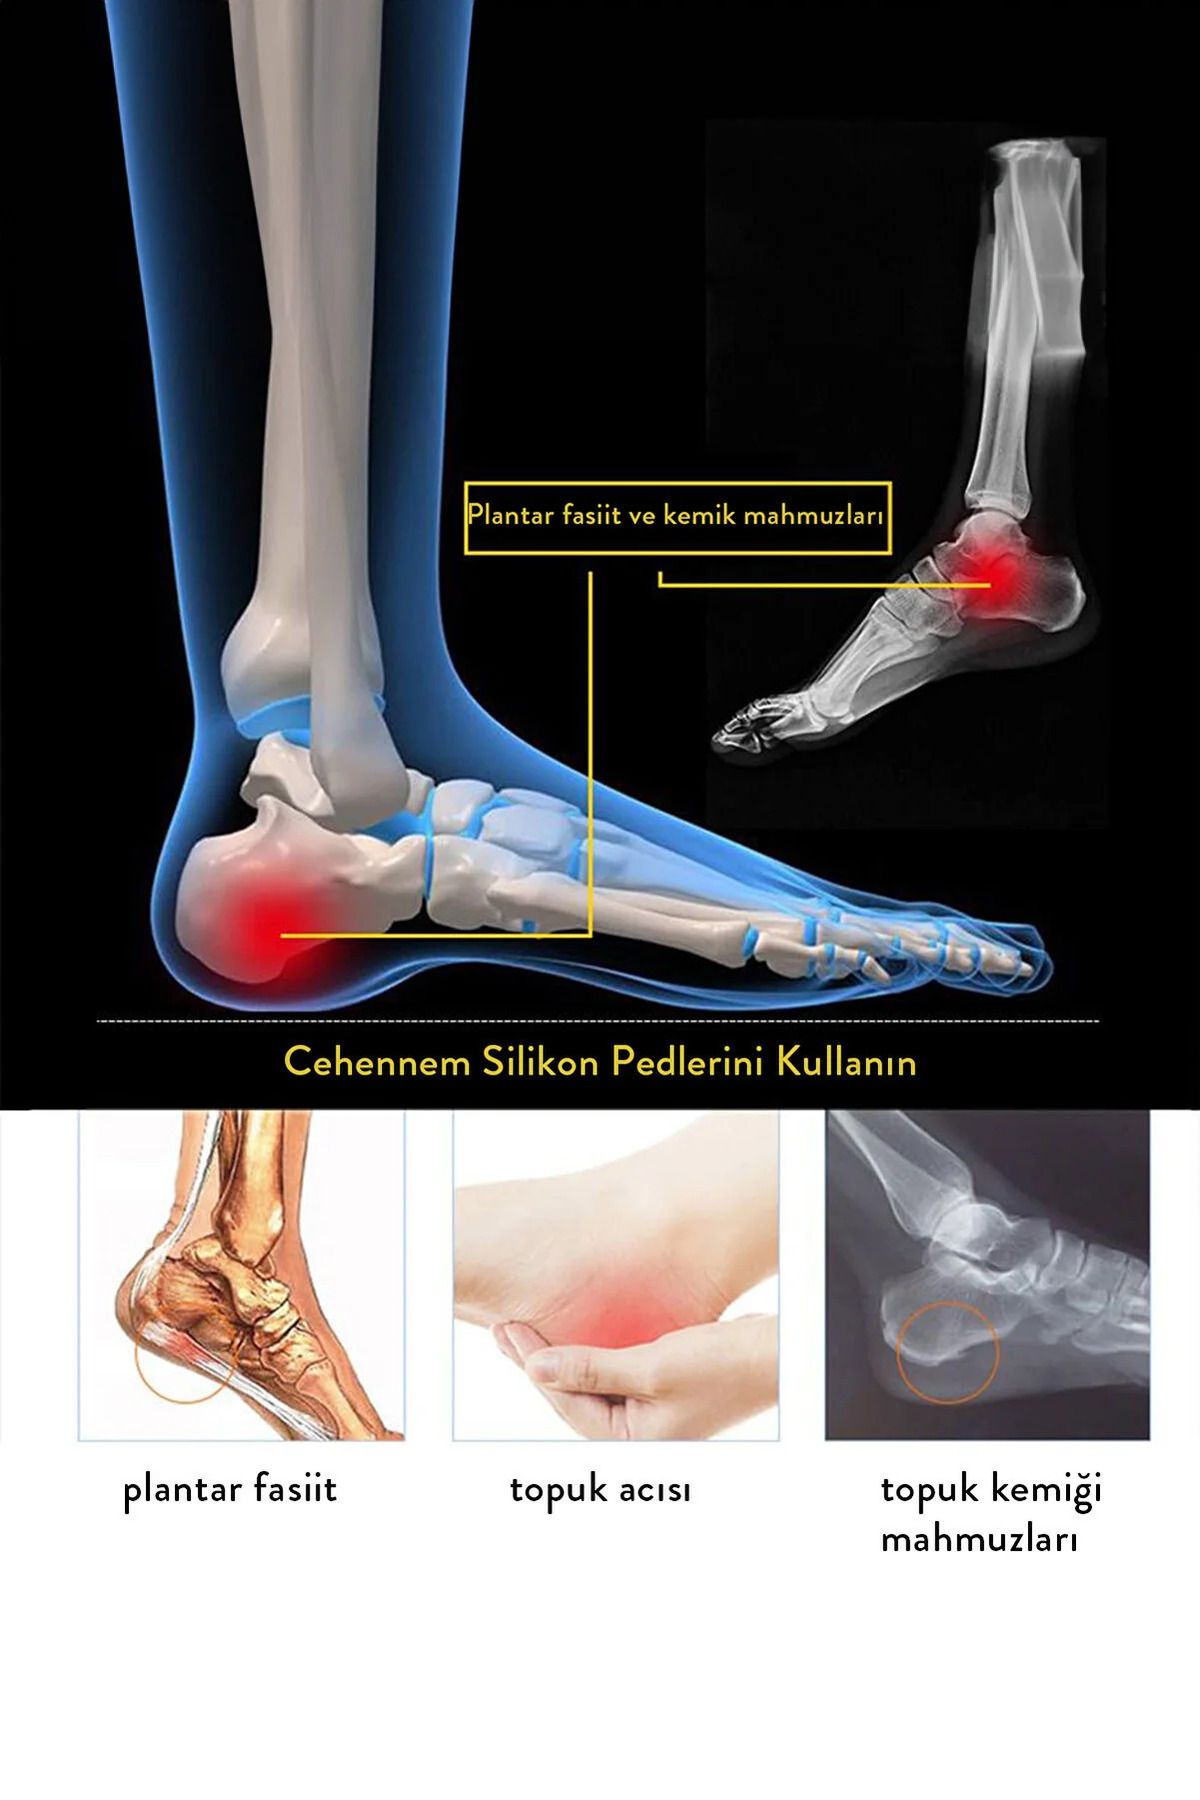

- هدف از استفاده : Topuk Dikeni